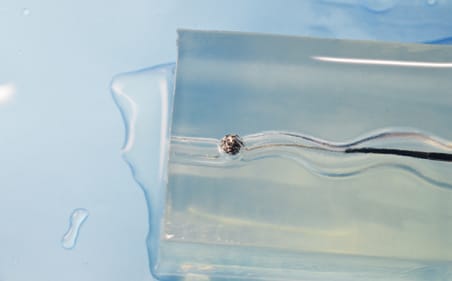

滑り性×透明

摩擦抵抗が低いため、デバイスをモデル内に通過させる際、生体と近い操作感を得ることが可能。高透明材のため、目視下でも、デバイスの挙動確認ができる。